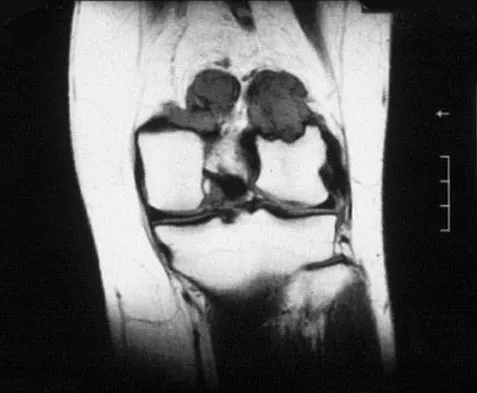

A 31-year-old woman has increasing pain and tightness in her right knee, with occasional stiffness and recurrent hemorrhagic effusions. MRI scans are shown in Figures 2a and 2b. What is the most likely diagnosis?

Explanation

PVNS is a rare inflammatory granulomatous condition of unknown etiology, and causes proliferation of the synovium of joints, tendon sheaths, or bursa. The disorder occurs most commonly in the third and fourth decades but can occur at any age. MRI provides excellent delineation of the synovial disease. Characteristic features of PVNS on MRI include the presence of intra-articular nodular masses of low signal intensity on T1- and T2-weighted images and proton density-weighted images. Synovial biopsy should be performed if there is any doubt of the diagnosis. Total synovectomy (open or arthroscopic) is required for the diffuse form, although recurrence is common. Rheumatoid arthritis and synovial chondromatosis are not typically associated with hemorrhagic effusions. De Ponti A, Sansone V, Malchere M: Result of arthroscopic treatment of pigmented villonodular synovitis of the knee. Arthroscopy 2003;19:602-607. Chin KR, Barr SJ, Winalski C, et al: Treatment of advanced primary and recurrent diffuse pigmented villonodular synovitis of the knee. J Bone Joint Surg Am 2002;84:2192-2202.